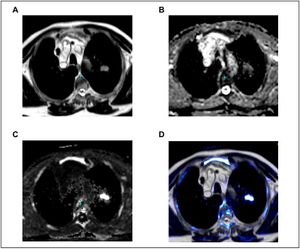

Publication: PLoS One. 2016 Sep 9;11(9):e0162816. PMID: 27612171 | PDF Authors: Fleckenstein J, Jelden M, Kremp S, Jagoda P, Stroeder J, Khreish F, Ezziddin S, Buecker A, Rübe C, Schneider GK. Institution: Department of Radiotherapy and Radiation Oncology, Saarland University Medical Center, Homburg, Germany. Background/Purpose: The study was designed to evaluate diffusion-weighted magnetic resonance imaging (DWI) vs. PET-CT of the thorax in the determination of gross tumor volume (GTV) in radiotherapy planning of non-small-cell lung cancer (NSCLC). MATERIALS AND METHODS: Eligible patients with NSCLC who were supposed to receive definitive radio(chemo)therapy were prospectively recruited. For MRI, a respiratory gated T2-weighted sequence in axial orientation and non-gated DWI (b = 0, 800, 1,400 and apparent diffusion coefficient map [ADC]) were acquired on a 1.5 Tesla scanner. Primary tumors were delineated on FDG-PET/CT (stGTV) and DWI images (dwGTV). The definition of stGTV was based on the CT and visually adapted to the FDG-PET component if indicated (e.g., in atelectasis). For DWI, dwGTV was visually determined and adjusted for anatomical plausibility on T2w sequences. Beside a statistical comparison of stGTV and dwGTB, spatial agreement was determined with the "Hausdorff-Distance" (HD) and the "Dice Similarity Coefficient" (DSC). RESULTS: Fifteen patients (one patient with two synchronous NSCLC) were evaluated. For 16 primary tumors with UICC stages I (n = 4), II (n = 3), IIIA (n = 2) and IIIB (n = 7) mean values for dwGTV were significantly larger than those of stGTV (76.6 ± 84.5 ml vs. 66.6 ± 75.2 ml, p<0.01). The correlation of stGTV and dwGTV was highly significant (r = 0.995, p<0.001). Yet, some considerable volume deviations between these two methods were observed (median 27.5%, range 0.4-52.1%). An acceptable agreement between dwGTV and stGTV regarding the spatial extent of primary tumors was found (average HD: 2.25 ± 0.7 mm; DC 0.68 ± 0.09). CONCLUSION: The overall level of agreement between PET-CT and MRI based GTV definition is acceptable. Tumor volumes may differ considerably in single cases. DWI-derived GTVs are significantly, yet modestly, larger than their PET-CT based counterparts. Prospective studies to assess the safety and efficacy of DWI-based radiotherapy planning in NSCLC are warranted. |

Multicenter Evaluation of Geometric Accuracy of MRI Protocols Used in Experimental Stroke